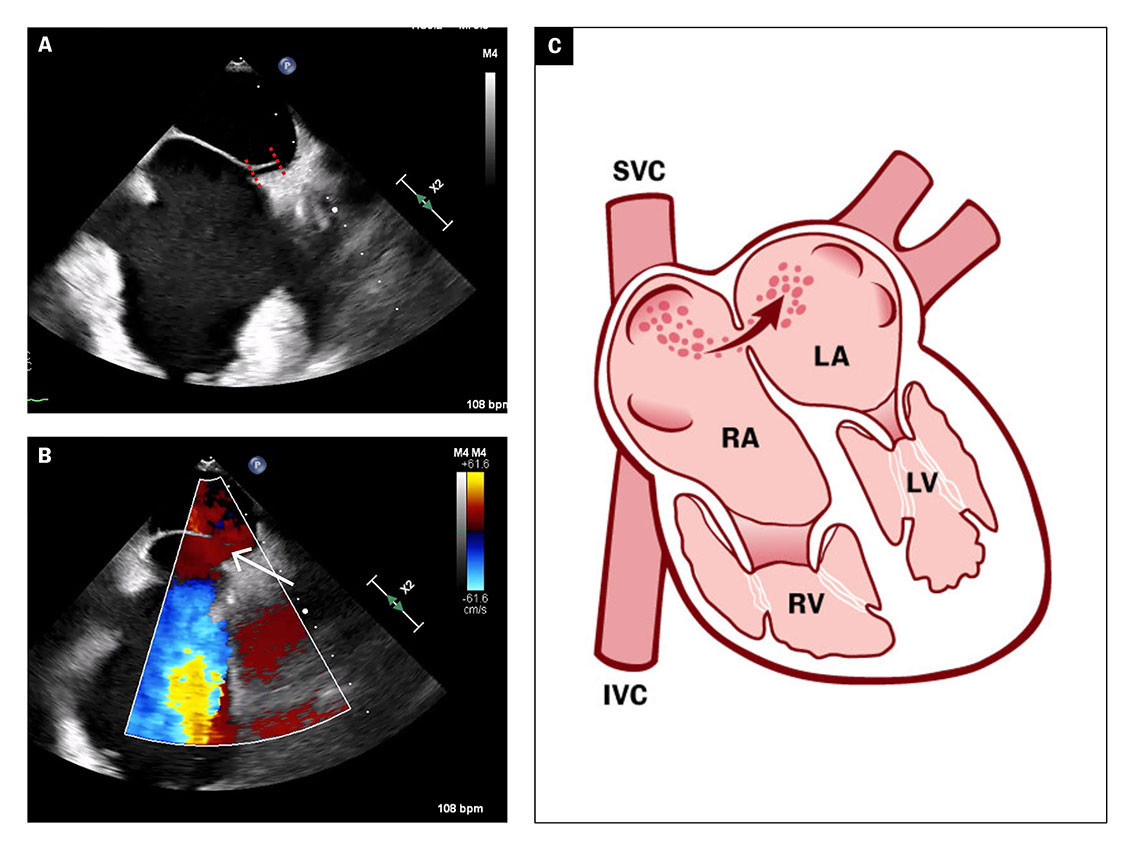

The transoesophageal echocardiogram showed patent foramen ovale with a tunnel length of 10 mm and an opening of 5 mm (Figure 3a), and a hypermobile atrial septum. Spontaneous right-to-left shunt of arterial emboli was observed using colour Doppler (Figure 3b).

The transoesophageal echocardiogram findings supported the suspicion of paradoxical embolisation with right-to-left shunt of atrial thrombus. Patent foramen ovale is usually verified by peripherally injected agitated saline and the Valsalva manoeuvre. Increased venous return to the right atrium would then cause a temporary increase in atrial pressure, which can lead to right-to-left atrial passage of microbubbles (Figure 3c).